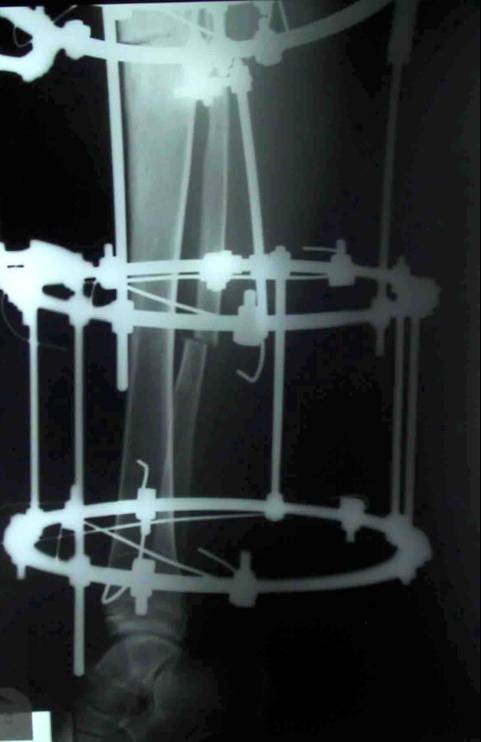

Blount disease is a developmental disorder characterized by disordered growth of the medial aspect of the proximal tibial physis resulting in progressive lower limb deformity. The deformity consists of varus, procurvatum, and internal rotation of the tibia, However, in the advanced stage of the disease, there is a bony bridge formation with medial plateau depression, joint instability, and leg length inequality, all of which have to be addressed by the proposed treatment. We treat this case by intra atticular osteotomy to elevation of medial plateau and another metaphyseal osteotomy to correct the varus and internal rotation deformities.

داء بلونت يطلق علي اعوجاج الساق المكون من هبوط باعلي الجزء الداخلي من اعلي عظمه الساق مع اعوجاج انسي بالساق و يتم علاج تلك الحالات بواسطه شقين عظميين احدهما خلال غظروف اعلي عظمه الساق والاخر بالجزء العلوي للساق مع الاستعدال التدريجي بواسطه مثبت خارجي مع العلم ان العلاج لا يرتبط بوزن المريض حيث يتم عمل العمليات بنجاح في الحالات السمنة الشديدة كما هو موضح بالصور